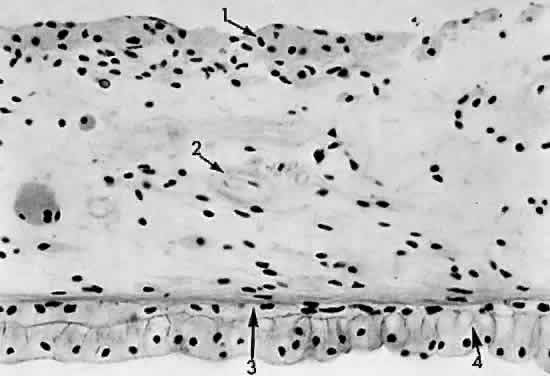

Fig. 14. Pars plana: 1, nonpigmented epithelium; 2, pigmented epithelium; 3, cuticular layer of Bruch's membrane; 4, avascular connective tissue layer; 5, elastic layer of Bruch's membrane; 6, vascular layer of pars plana (× 225, KEI 8982B).

The pars plana is a 4-mm flat band area extending posterior to the ciliary processes. It joins with the peripheral cystoid retina at the ora serrata (Fig. 13). The nonpigmented epithelial layer flattens anteriorly but becomes columnar posteriorly as it approaches the retina. The pigmented epithelial layer of the pars plana continues as the pigmented epithelium of the retina. A ridged cuticular layer (the reticulum of Muller) lying adjacent to the pigmented epithelium layer of Bruch's membrane at the ora serrata is an avascular connective tissue that separates the inner cuticular layer from the outer elastic layer of Bruch's membrane in the pars plana region (Fig. 14).

The nonpigmented epithelium of the pars plana secretes the acid mucopolysaccharide component of the vitreous body at its basal attachment. The lens zonules are firmly attached to the nonpigmented epithelial cells of the pars plicata, so that during cataract surgery traction may cause detachment of the nonpigmented epithelium if the zonules are broken.